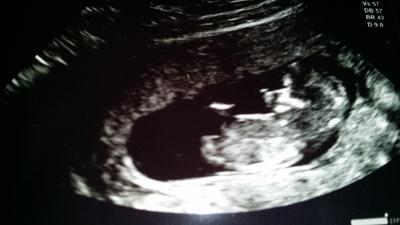

Hey liebe Mamis..... ich bin ja jerzt in der 13 ssw (fast 24ssw) und vor ein paar Tagen wieder das Ding...... Schmierblutungen... Ich hab die Kriese bekommen.Dachte jetzt im 4.Monat hört das auf aber nix.... Sofort beim Arzt angerufen und musste aber erst nächsten Tag hin weil es nicht soviel war und es war schon ziemlich spät.Ende vom Lied.... Baby gehts (Gott sei daaank) wunderbar. Wohl immernoch ne altblutung die stotterweise abläuft.Nackenfalte war super und zwischen den Beinen war nix zu sehn ;-P Aber noch abwarten...ist ja noch etwas früh.Aufjedenfall geht dem Baby super und das ist das wichtigste.... Nur die Kotzerei...die hört eiiiiiiinfach nicht auf :-( mano.... So und jetzt noch ein Bildchen... Arme und Beine kann man auf dem Foto net sehen.

War ja nur am tanzen ^^

Das Bildchen sieht Super süß aus

Und dann immer diese schönen Bilder....noch mehr zum verlieben

Unsere tanzenden Mäuse